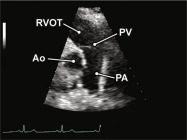

| 2.5. Mặt cắt trục dài cạnh ức qua đường ra thất phải |

||||||||

|

|

Cửa sổ siêu âm cạnh ức

Mặt cắt trục dài cạnh ức Ngửa và xoay đầu dò về phía đường ra thất phải/ |

Đường ra thất phải (RVOT) Van động mạch phổi (PV) Động mạch phổi (PA) |

|||||